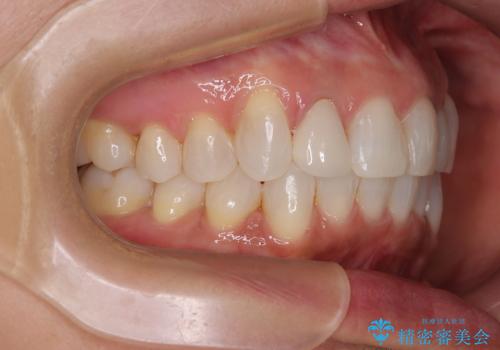

前歯のデコボコとむし歯治療の跡 インビザライン矯正とオールセラミッククラウン治療

- 前歯のセラミッククラウンの縁が見えることが気になってから、デコボコも気になるようになってきたとのことで来院された患者様です。

デコボコの程度は中等度であったため、インビザライン・モデレートパッケージにて歯列を整えることとしました。

セラミッククラウンの装着されていた前歯と、大きな修復治療の跡がある反対側の歯は、矯正治療後に補綴治療を行うこととしました。

奥歯の欠損はインプラント、ブリッジ、入れ歯のどれにすれば良いかを決められず、仕事が非常にお忙しいこともあり、保留としたまま治療を終えることとなりました。

後戻りのリスクがあるため、なるべく早めに欠損補綴治療を開始する予定です。